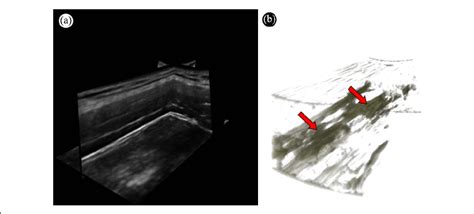

3D rendering of a MTrP. (a) Multiplanar view of...